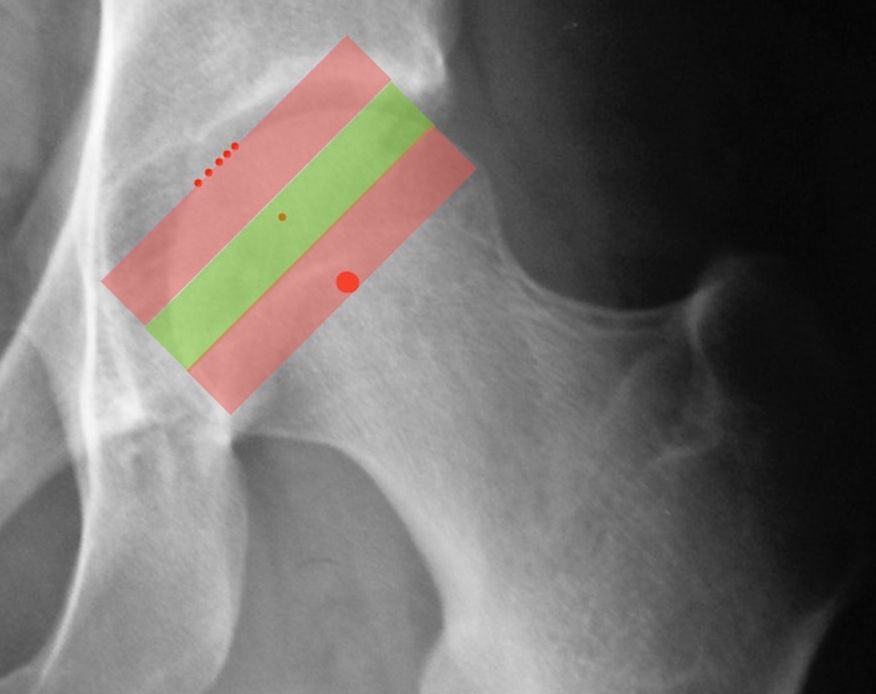

Martin Beck (26) has recently described another excellent sign of instability, known as the FEAR index (Femoro Epiphyseal Acetabular Roof) which is the angle between the acetabular sourcil and the femoral head physeal scar (Fig. 12).

The idea came from the fact that during adolescence, the epiphyseal growth plate of the femur orients itself perpendicularly to the forces applied to it, and thus to the acetabulum. If the hip is unstable and subluxes, the growth plate is no longer parallel to the roof of the acetabulum. A recent study has validated this radiological sign in a group of 150 patients undergoing arthroscopy. The FEAR index was significantly more positive in the unstable hips compared with the stable ones (27). Finally, another excellent sign to be aware of, again described by Marc Safran, is the Cliff Sign (28). An unstable hip will nearly always have a very narrow neck and a head that is no longer a perfect circle, losing some sphericity where it ‘exits’ the acetabulum i.e. around its lateral aspect (Fig. 15). The larger the lateral empty space, the greater the sign.